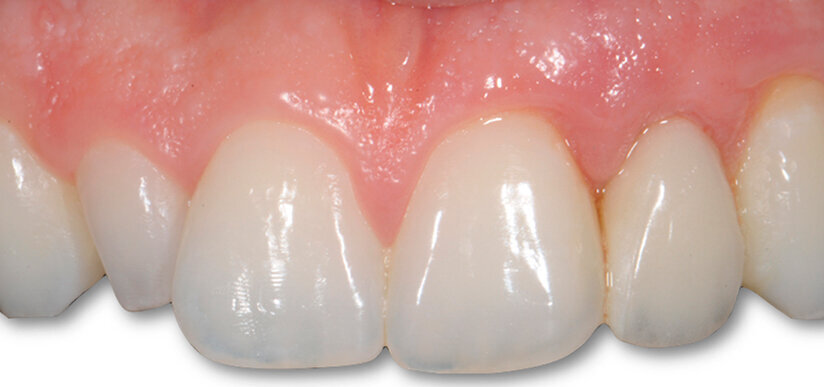

A guarigione dei tessuti molli è stata rilevata l’impronta di posizione per la realizzazione dell’abutment definitivo e la costruzione dei provvisori, sia per la corona su impianto dell’elemento 22 sia la veneer dell’elemento 12. Eseguito un adeguato condizionamento dei tessuti molli, sono state poi posizionate a distanza di 10 mesi la corona definitiva a livello di elemento 22 in zirconia integrale a veneer in ceramica a livello di elemento 12 (Figg. 5-6c).

Fig. 6a - Corona cementata.

Fig. 6c - Controllo dei tessuti molli a un mese.

Fig. 8a - Caso concluso con veeners in ceramica a livello del 22.